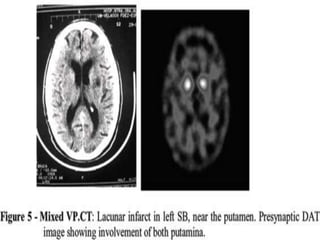

•IMAGINGFOR

PARKINSON’S DISEASE